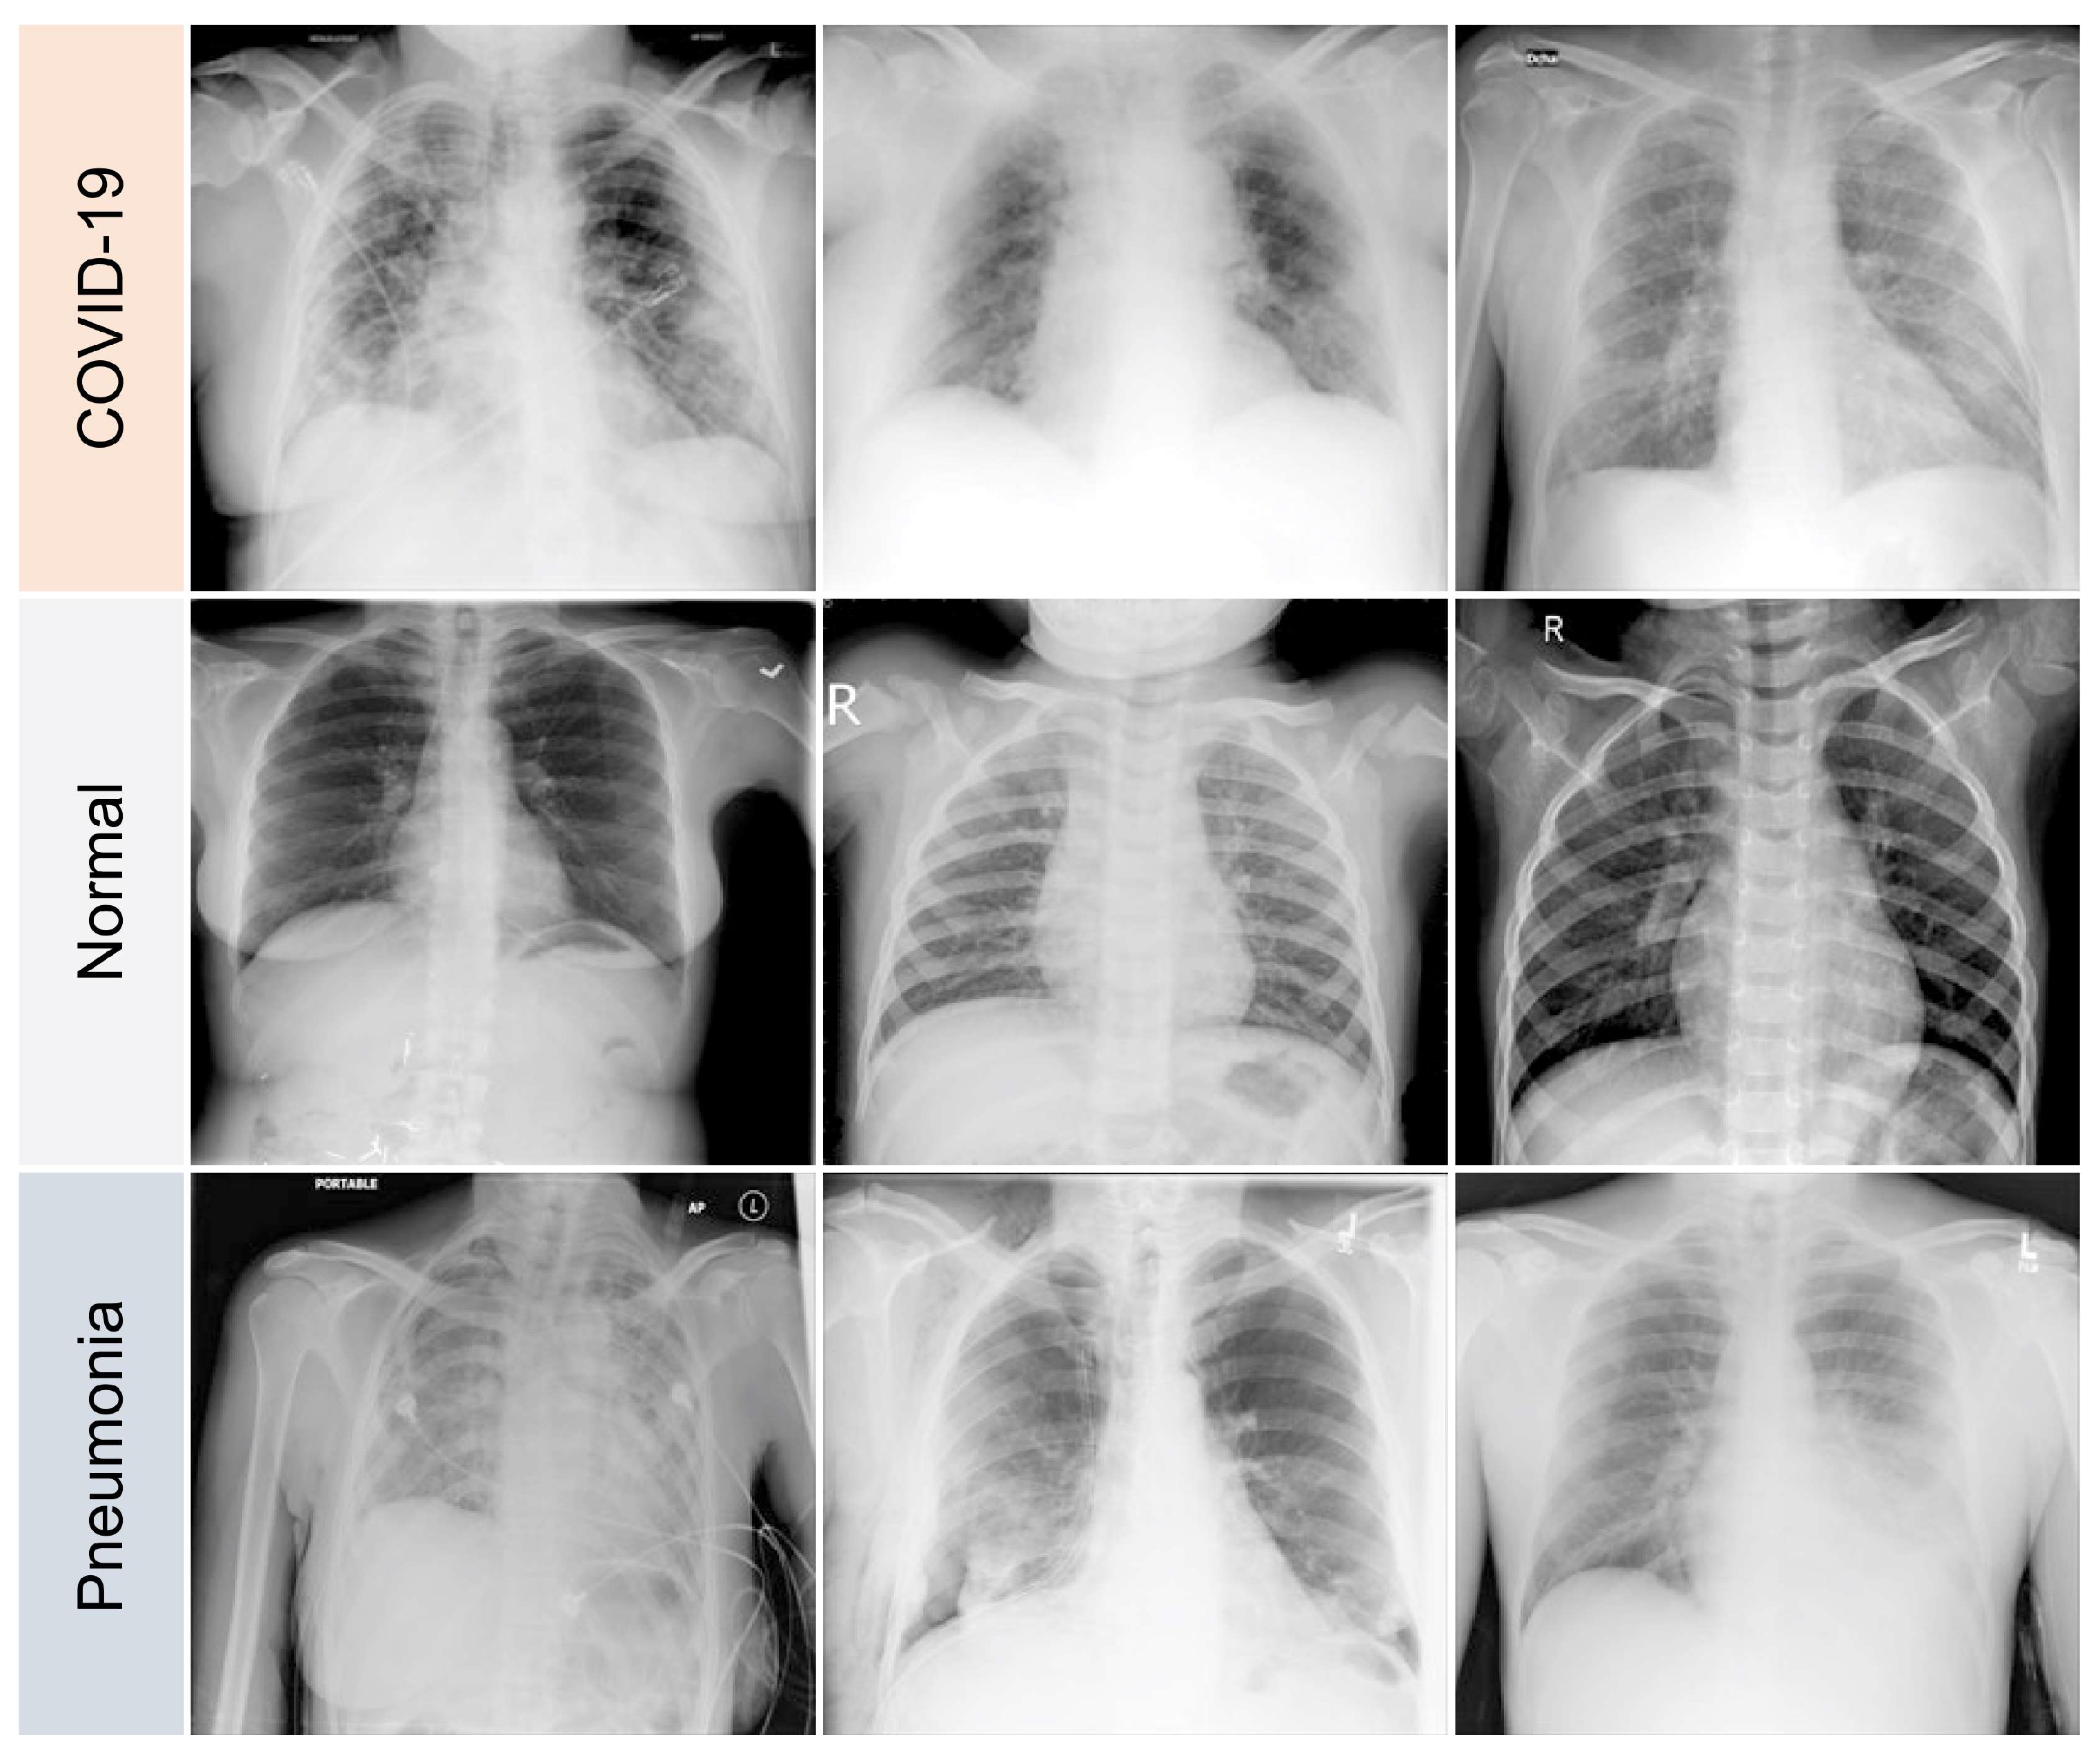

3.1. Data Preparation

- 11,956 COVID-19 samples

- 11,263 cases of pneumonia caused by viruses or bacteria that are not COVID-19

- 10,701 normal (healthy) samples

4.1. Data Processing

- GGOs.

- Odd paving pattern.

- Consolidation of the airspace.

- Thickening of bronchovascular bundles.

- Traction bronchiectasis.

- Reticular opacities.

- Vascular thickness.

- Additional widespread distribution along the bronchovascular bundles.

- Thickness in bronchial wall.

4.2. Learning COVID